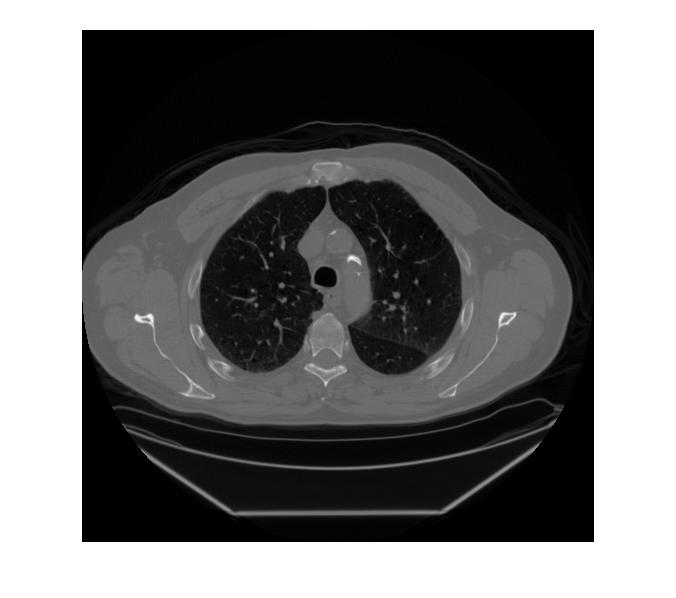

II-C CT Image Visualization

We begin by visually comparing the ROI selected by the WFDM method to that of the baseline method. Fig. 3 demonstrates the baseline thresholding method from Fig. 1 now applied to an image taken from a patient at 48m​Aπ‘šπ΄mA tube current. Fig. 3(a) is the original image scaled to [0,1]01[0,1] and Fig. 3(b) is the mask acquired by thresholding pixel intensities such that [0.4,0.7]=10.40.71[0.4,0.7]=1 and the remaining pixels are set to 00. The ROI shown in Fig. 3(c) results from further narrowing the threshold so that [0.5,0.6]=10.50.61[0.5,0.6]=1 and the remaining pixels are set to 00. In addition, these threshold ranges were chosen empirically, hence the baseline method is not generalizable.

Conversely, applying WFDM to the same CT image shown in Fig. 3(a) and thresholding at [q<IDΒ―4]delimited-[]π‘žΒ―subscriptID4[q<\frac{\overline{\rm I_{D}}}{4}], where IDΒ―Β―subscriptID\overline{\rm I_{D}} is the mean distance in IDsubscript𝐼𝐷I_{D}, results in the mask and corresponding ROI-LV shown in Fig. 4, respectively. Here, we observe the qualitative variations between the original image and the masked ROI-LV image. First, edges, as well as regions of high spatial variation such as the spine, have been removed. Second, the selected regions are not necessarily of the same absolute pixel intensity, as compared with the ROIs shown in Fig.3. Finally, the masked ROI-LV region in Fig. 4(b) is selected by relative thresholding as opposed to fixed intensity thresholding in the baseline method. Thus, the proposed WFDM based ROI-LV masking method is generalizable.

Refer to caption

Figure 3: A CT image from the patient data imaged at 48m​Aπ‘šπ΄mA tube current. (a) The original CT image, (b) a mask of ROI acquired by fixed thresholding [0.5,0.6]=10.50.61[0.5,0.6]=1, and (c) a mask of ROI acquired by fixed thresholding [0.525,0.575]=10.5250.5751[0.525,0.575]=1.

Figure 4: The same CT image as in Fig. 3(a) after processing with WFDM. (a) A mask ROI-LV and (b) the masked ROI-LV are observed.